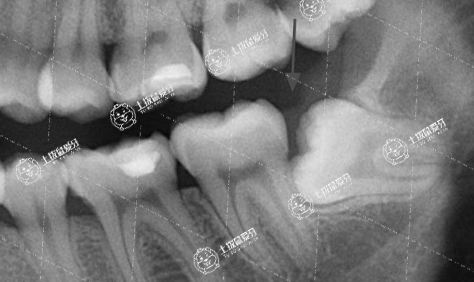

2、智齒不能正常萌出

這一種類型的牙齒,通常埋在牙槽骨的里面,后期繼續(xù)生長(zhǎng)會(huì)擠到前面大牙,若沒有拔除智齒會(huì)容易造成牙齒移位導(dǎo)致效果反彈。但是如果你智齒阻生或者頻繁發(fā)炎,不管有沒有做牙齒矯正,只要智齒給你造成了困擾,也是需要拔除的。